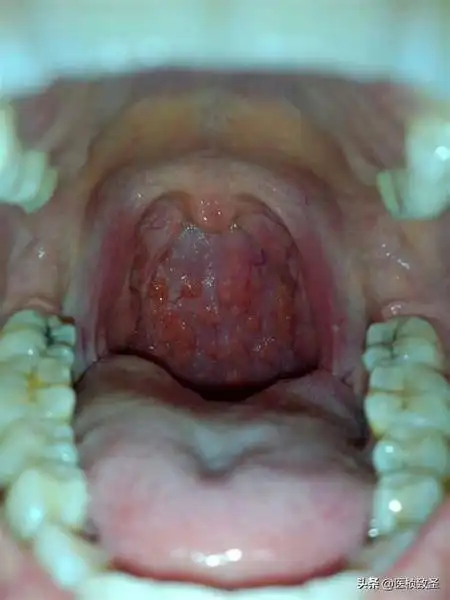

扁桃体炎

然后对着镜子张开嘴巴就能看到是否肥大了,正常人的扁桃体如下图所示

我喉咙的扁桃体这样是不是很严重了?